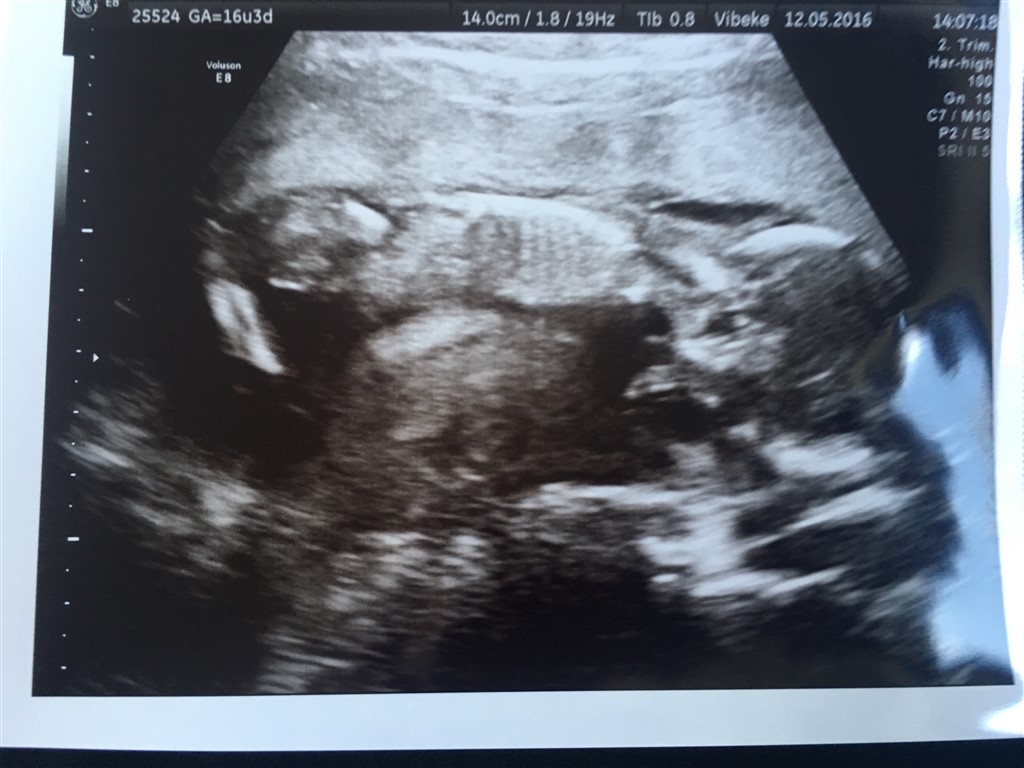

Vil starte med at sige at alt er som det skal være med babyen..

Næstved kunne ikke se kønnet, men babyen er præcis som den skal være. Flot vægt og flot længde. Hjerte, hjerne, lårben alt er lige præcis efter skalaen. Den danser rundt derinde. I forhold til Isaac er der meget meget mere liv denne gang.

Billederne blev knap så gode, for hun er altså en putterøv

Vedhæftede fotos (klik for at se i fuld størrelse)